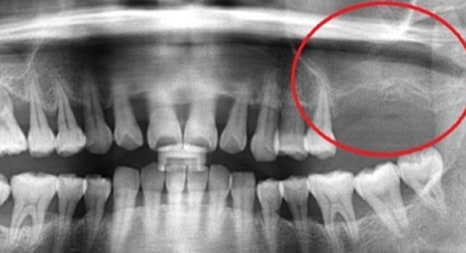

위 턱뼈는 아래턱뼈보다 얇고 코와 뺨 사이 빈 공간 (상악동)이 있어서 임플란트를 식립할 경우 실패 가능성이 높아집니다.

부족한 뼈를 보충하기 전 상악동 거상술을 시행할 때 노하우가 부족하면 임플란트 식립 후 쉽게 빠져버리거나 입 천장 쪽에 천공이 나는 부작용이 생기기 때문에 치과 진료 중 난도가 높은 과정에 속합니다.

본 환자분은 부족한 잇몸뼈를 보충하는 뼈 이식술과 난도 높은 상악동 거상술을 진행해 안정적인 임플란트 수술을 마쳤습니다.